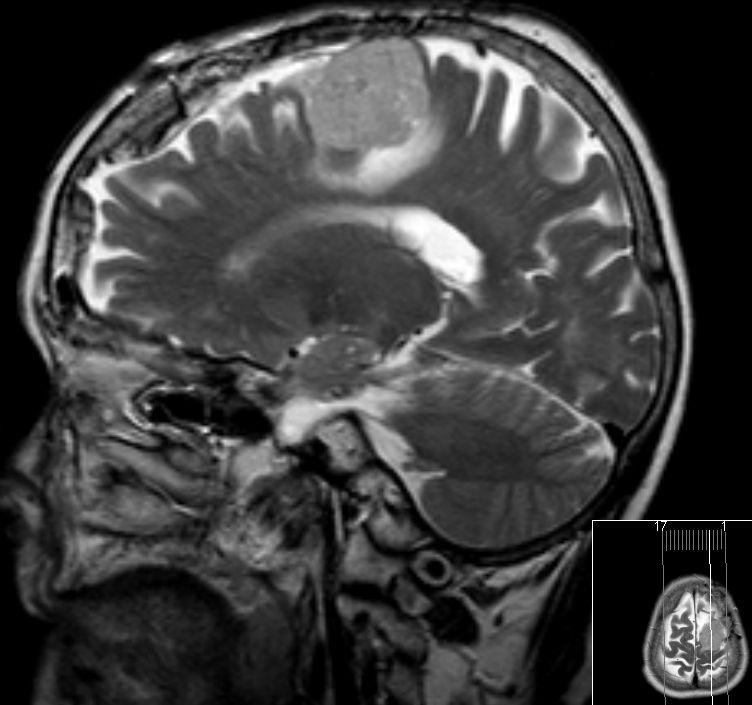

Klinik Scharf begrenzt, homogen, extraaxiale Raumforderung. Breite Verbindung zur Dura. Nach KM homogenes Enhancement. 20% Verkalkungen oder Schädelveränderungen (Hyperostose, Osteolyse). Wenn alle Kriterien erfüllt sind, ist eine histologische Sicherung entbehrlich.

Diagnostik Fallbeispiele

sekretorisches M. seltene, gutartige Sonderform. In 70% starkes perifokales Hirnödem, in 50% hemisphaerisches Hirnödem. Überwiegend ältere Patienten. Typisch basaler Sitz.